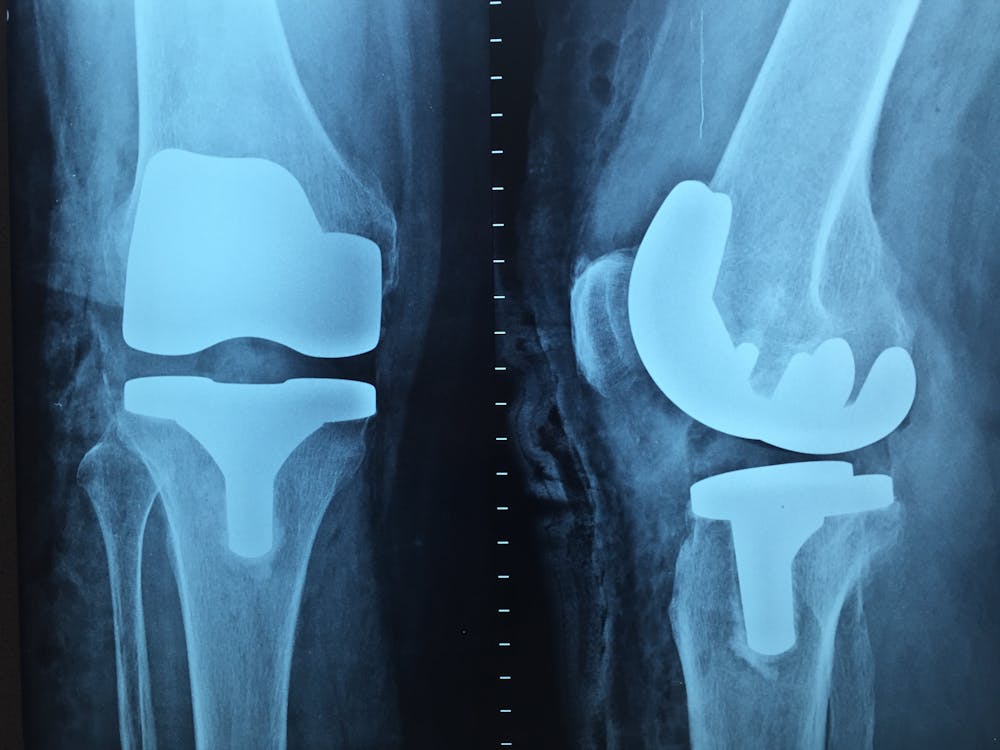

Knee Osteoarthritis: The Strongest Evidence

Knee OA is where PRP has the most robust clinical trial data, and it's where I'm most confident recommending it. Multiple systematic reviews and meta-analyses have found that PRP outperforms both hyaluronic acid (HA) injections and corticosteroids for pain reduction and functional improvement in knee osteoarthritis, with effects that are more durable -- typically lasting 12 months or longer compared to the three to six month window of corticosteroids.

A 2021 meta-analysis of 18 randomized controlled trials concluded that PRP produced superior outcomes to HA at six and twelve months for both pain and function in knee OA. Importantly, PRP appears to have a disease-modifying effect that corticosteroids lack -- rather than simply suppressing inflammation, PRP growth factors promote cartilage cell survival, reduce inflammatory cytokines locally, and support the synovial environment. Repeated corticosteroid injections actually accelerate cartilage degradation over time. PRP doesn't.

For mild to moderate knee OA, a series of two to three PRP injections over four to six weeks is the evidence-supported protocol. Grade 4 (bone-on-bone) OA is a harder target and outcomes are less predictable, though some patients still benefit.